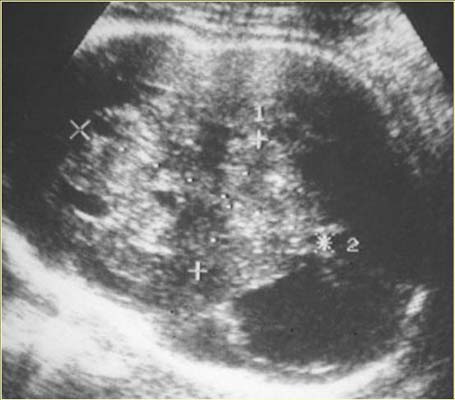

Tératome intra-cranien